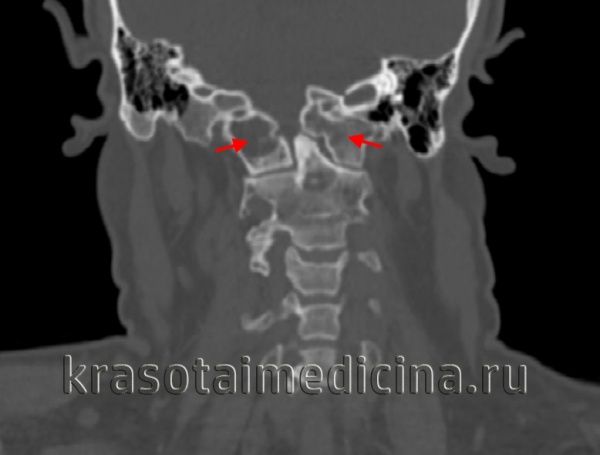

(Слева) КТ, фронтальный срез: латеральная дислокация боковой массы С1. Верхушка зубовидного отростка находится у края большого затылочного отверстия в связи с потерей высоты атланта. Обратите внимание на повреждение атланто-затылочного сустава и вывих в дугоотростчатом суставе С1-С2. Также здесь имеет место перелом левой суставной колонны С2.

(Справа) КТ, сагиттальный срез: часть взрывного перелома С1, линия которого проходит через боковую массу позвонка, подчеркивая роль аксиальной нагрузки со стороны мыщелка затылочной кости в механизме возникновения данного повреждения.